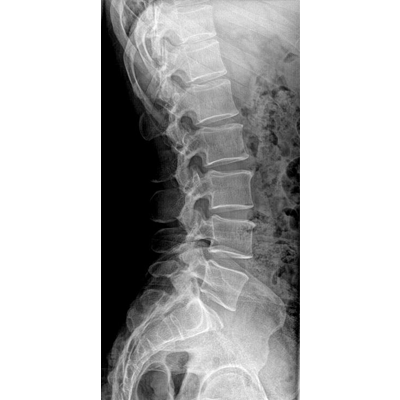

●大尺寸非晶硅平板探測器。

●探測器可以大范圍轉(zhuǎn)動,大尺寸有效探測面積,可滿足人體多部位攝影需求。